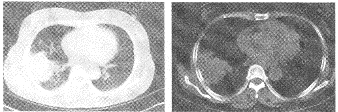

- 多项选择题3.为进一步了解病灶性质,行胸部CT扫描, 如图,则图中支持肺脓肿诊断的CT征象包括

A、跨叶分布的大片状高密度影

B、支气管充气征

C、液气平面

D、少量胸腔积液

E、纤维索条影

F、病灶密度不均其内见较低密度区